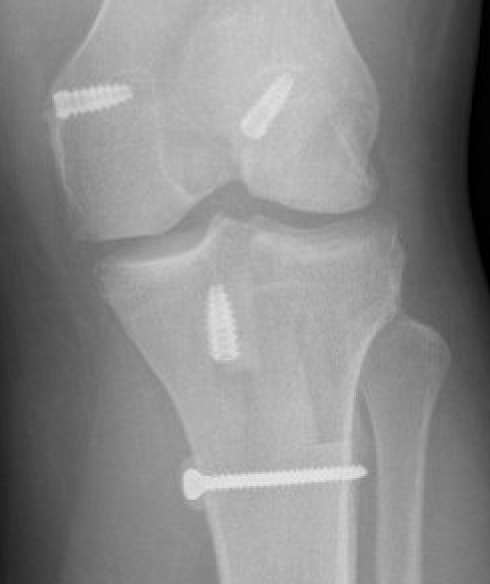

Bony MCL Avulsion

Elevate VMO and repair with staples or screw

3. Reconstruction of MCL and posteromedial corner

A. Single bundle anatomic allograft MCL reconstruction (no POL)

ACL / MCL

Marx technique MCL reconstruction with tendoachilles allograft PDF